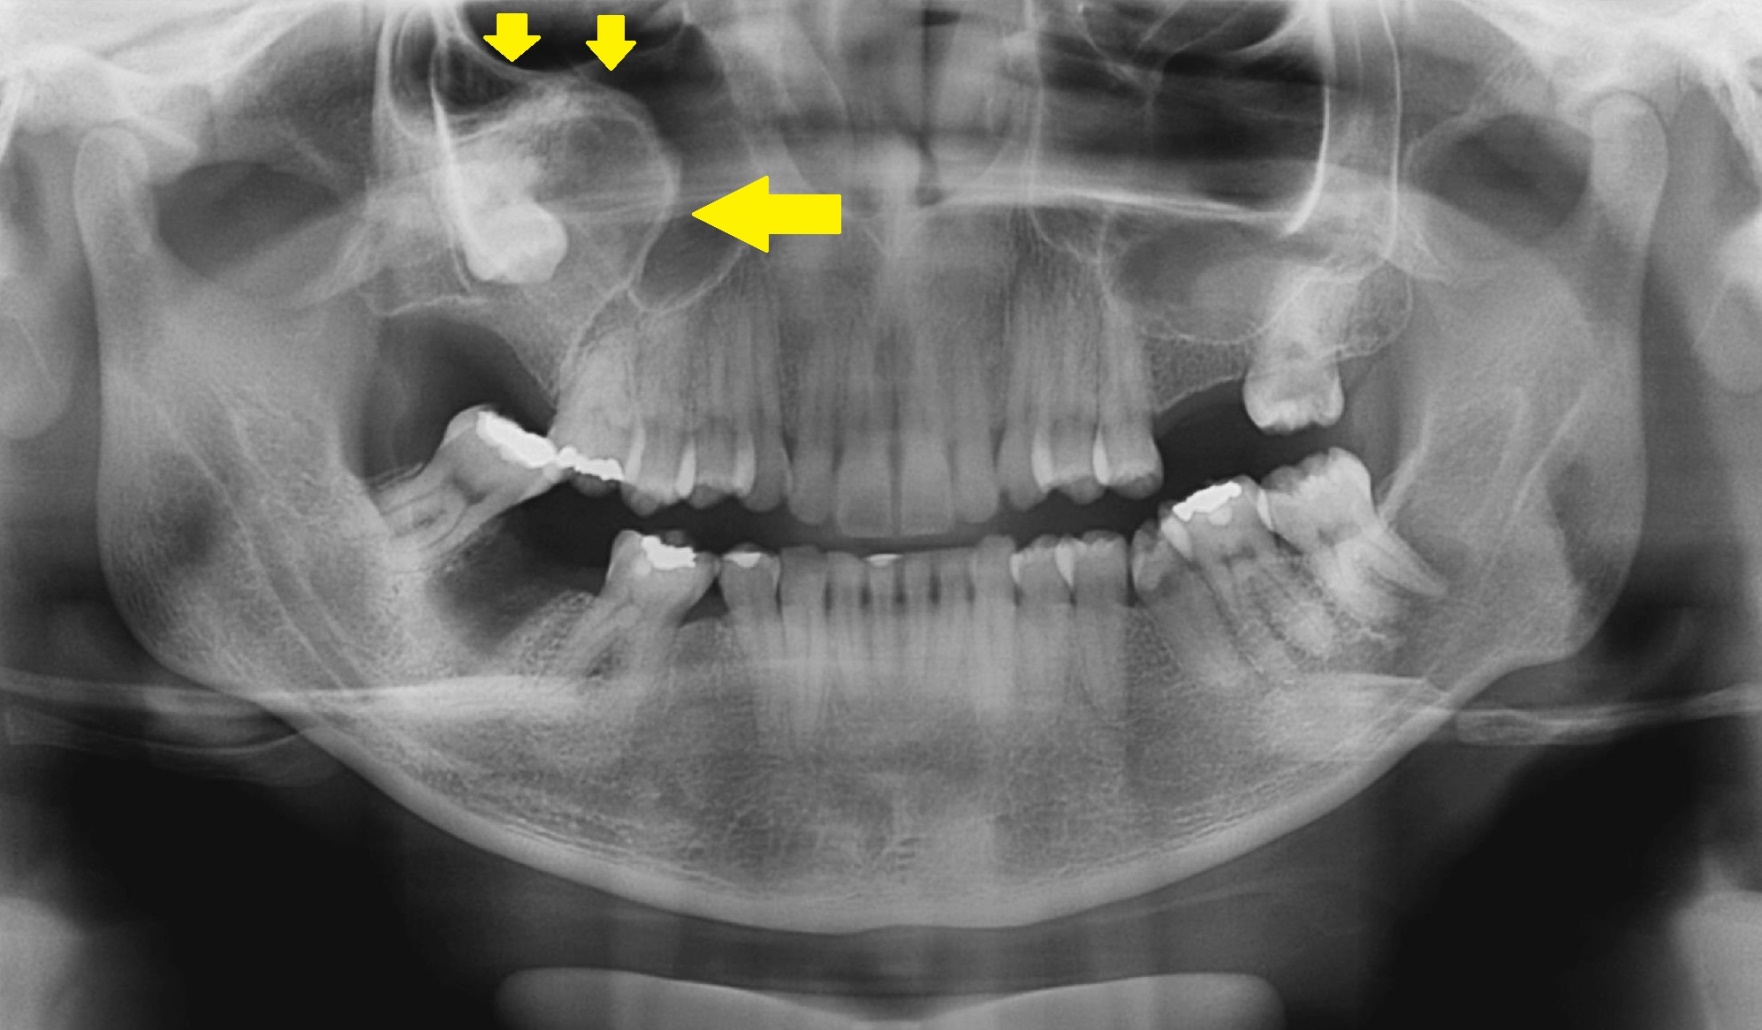

Raios X Seios Da Face – Método De Caldwell - Concursos Já Brasil

seios raio seio faciais sinusite nomes os raios cavidades nasais radiologia radiografia alternativos são